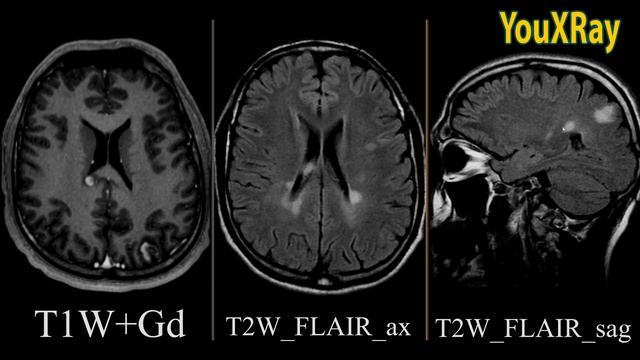

1. 0:05 Рассеянный склероз: что это за болезнь.